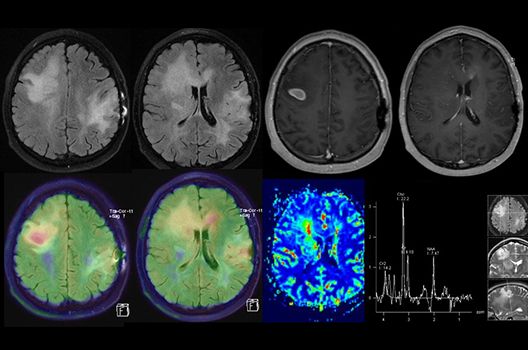

Die Schwerpunkte in der MR-Forschung liegen in der multiparametrischen und funktionellen Bildgebung bei onkologischen und anderen, neuroradiologischen Fragestellungen und umfassen die Anwendung modernster MR-Verfahren sowie die Untersuchung an Hochfeld-Geräten.

Die Hybridbildgebung mittels PET/MRT spielt insbesondere in der onkologischen Bildgebung eine wichtige Rolle. Eine mögliche Fragestellung ist die Unterscheidung zwischen einem Tumorrezidiv oder therapeutisch assoziierten Veränderungen insbesondere dann, wenn diese Frage mittels MRT alleine nicht beantwortet werden kann.

Die bildgebende Diagnostik und Verlaufsbeurteilung von Tumoren des Nervensystems ist einer der klinischen und Forschungsschwerpunkte unserer Abteilung. Eine besondere Bedeutung kommt der Hybrid-Bildgebung zu. Das Universitätsklinikum verfügt über einen integrierten Ganzkörper-PET/MRT-Scanner, der die Vorteile der MRT-Bildgebung und der Positronenemissionstherapie (PET) vereinigt. Aufgrund der langjährigen klinischen Arbeit und Forschungstätigkeit mit diesem Gerät hat die Neuroradiologie Tübingen maßgeblich zur Etablierung dieses Verfahrens beigetragen. Auch weiterhin forschen wir intensiv an neuen Methoden zur frühen Einordnung von Tumoren und insbesondere Tumorrezidiven, die mit anderen Methoden häufig nicht erfasst werden können.